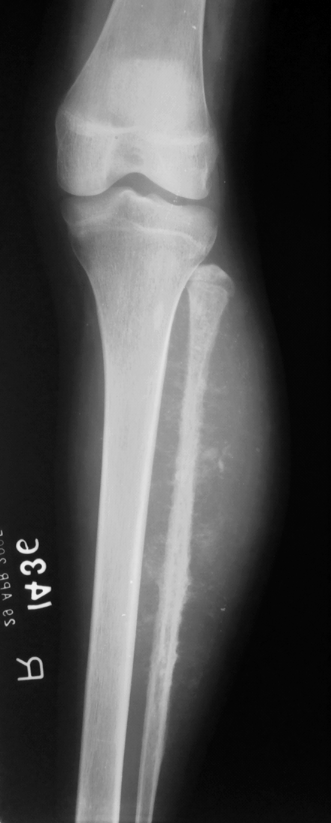

VERY HIGH A/W ACL

The arcuate sign is often a subtle but important finding on knee x-rays and represents an avulsion fracture of the proximal fibula at the site of insertion of the arcuate ligament complex, and is usually associated with cruciate ligament injury (~90% of cases) 2. The fracture fragment is attached to the lateral (fibular) collateral ligament, the biceps femoris tendon, or both.